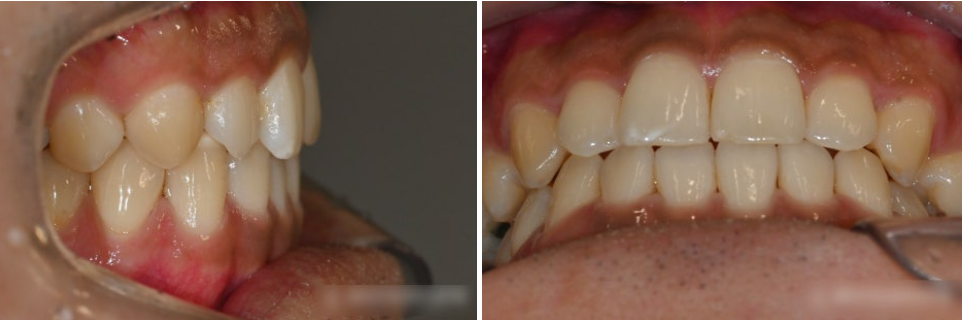

『치료 후』

부분교정과 임플란트 수술을 마친 후 모습입니다.

치아를 이동시켜 공간을 만드는

부분교정은 비교적 빠르게 마무리되었습니다.

그와 동시에 앞니도 가지런히 배열 완료되었습니다.

처음엔 좁았던 발치 공간이

제대로 확보되면서

지르코니아 보철(크라운)이 계획대로

예쁘게 잘 들어간 모습입니다.